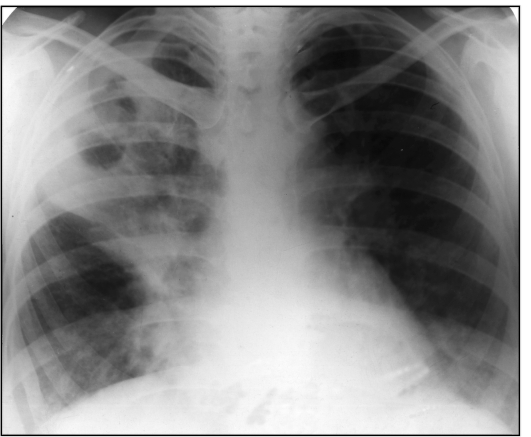

Диагностика инфильтративного туберкулёза включает в себя сбор анамнеза, физикальное обследование, анализ крови и рентгенологическое обследование. При проведении аускультации, как правило, характерные изменения можно определить лишь на стадии распада инфильтрата. При этом обнаруживается притупление перкуторного звука в области поражения, а также влажные и звучные хрипы. При помощи рентгенологического обследования определяется локализация инфильтрата (наиболее часто это I, II и VI сегменты). При проведении анализа крови обнаруживается незначительный сдвиг в лейкоцитарной формуле и небольшое ускорение СОЭ.

Кроме того, инфильтративный туберкулёз классифицируется по типу и локализации инфильтрата. Различают следующие виды инфильтратов:

- бронхолобулярный инфильтрат - располагается в I или II сегменте верхней доли лёгкого, имеет неправильную округлую форму, его диаметр равен 1-3 см;

- округлый инфильтрат - обладает округлой овальной формой, располагается в I-II или VI сегменте;

- облаковидный инфильтрат - затемнение неравномерной формы с расплывчатыми контурами;

- лобит - воспалительный процесс во всём лёгком с множественными казеозными очагами;

- перисциссурит - представляет собой облаковидный инфильтрат, который располагается возле междолевой борозды.